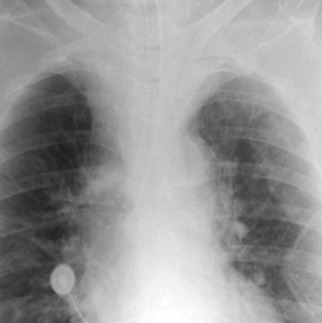

Complications of intubation ( Figs. 25-1 to 25-10 ) and ventilation that are apparent on a chest radiograph are often potentially life-threatening and should be excluded on every radiograph, both immediately following intubation and with each subsequent radiograph. These possibilities are listed in the following sections.

Barotrauma

- □

Pneumothorax

Pneumomediastinum

Pneumopericardium

Subcutaneous emphysema